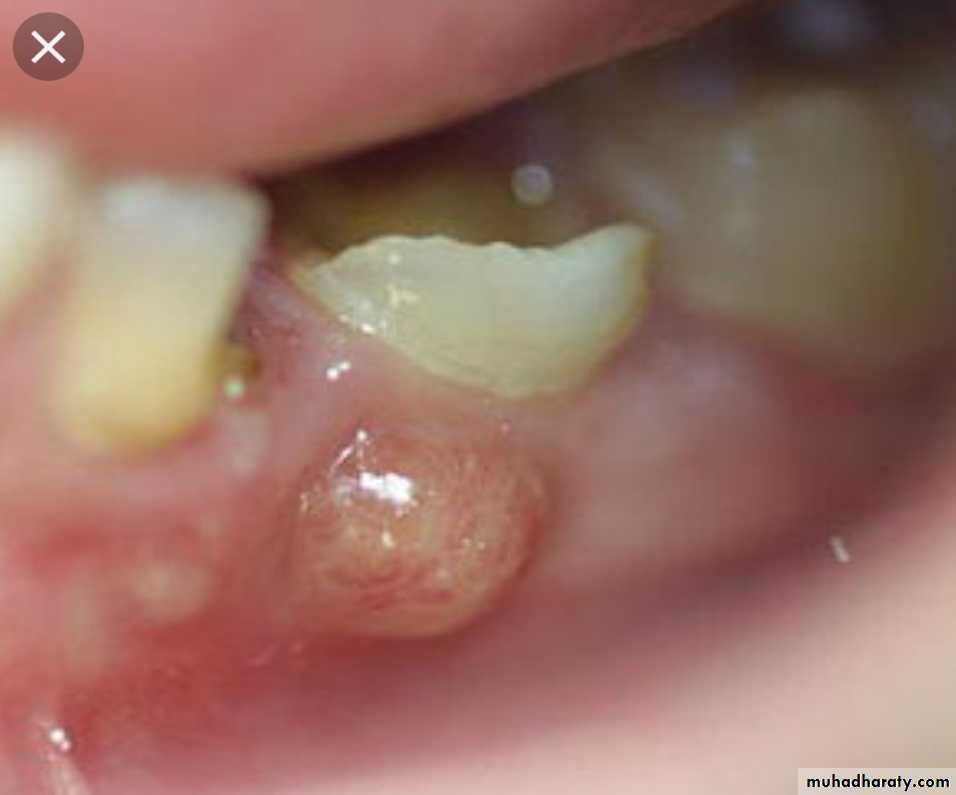

3- Pseudomembranous : characterized by formation of peudomembrane as in diphtheria.4- Pyogenic or suppurative: pus producing . e.g. Abscess

Pus is a creamy fluid consist of neutrophil, pus cell (dead neutrophil) necrotic tissue, bact. & fluid.

Localized collection of pus in tissue is called abscess